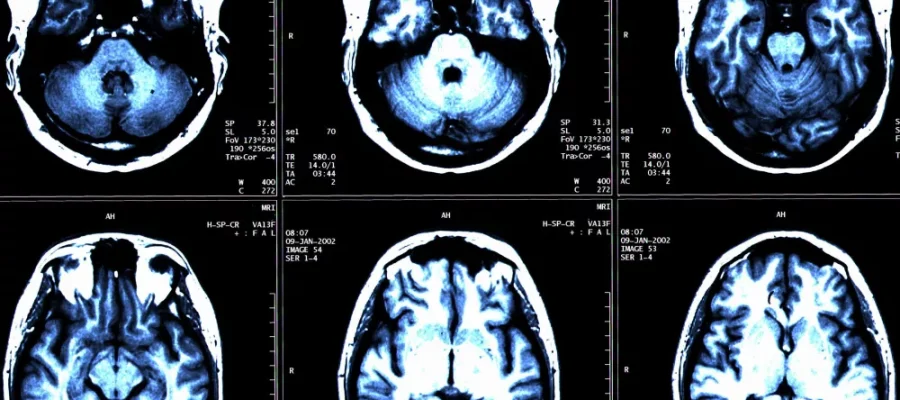

“Brain Segmentation with Artificial Intelligence” is a fully automatic and FDA-approved software helping physicians in the differential diagnosis of the most common types of dementia.

YBuilt with Artificial Intelligence, this fully automated and FDA-approved software assists physicians in the differential diagnosis of the most common types of dementia: Alzheimer’s Disease (AD), Vascular Dementia (VaD), Dementia with Lewy Bodies (DLB), and Frontotemporal Dementia (FTD).

The Brain Segmentation with Artificial Intelligence output consists of a short report with normative reference values and color-coded segmentations in DICOM format to help the physician report and conceptualize the patient’s condition.

Some structural MRI features have a positive predictive value for AD and non-AD dementia and can be used in the differential diagnosis of dementia.